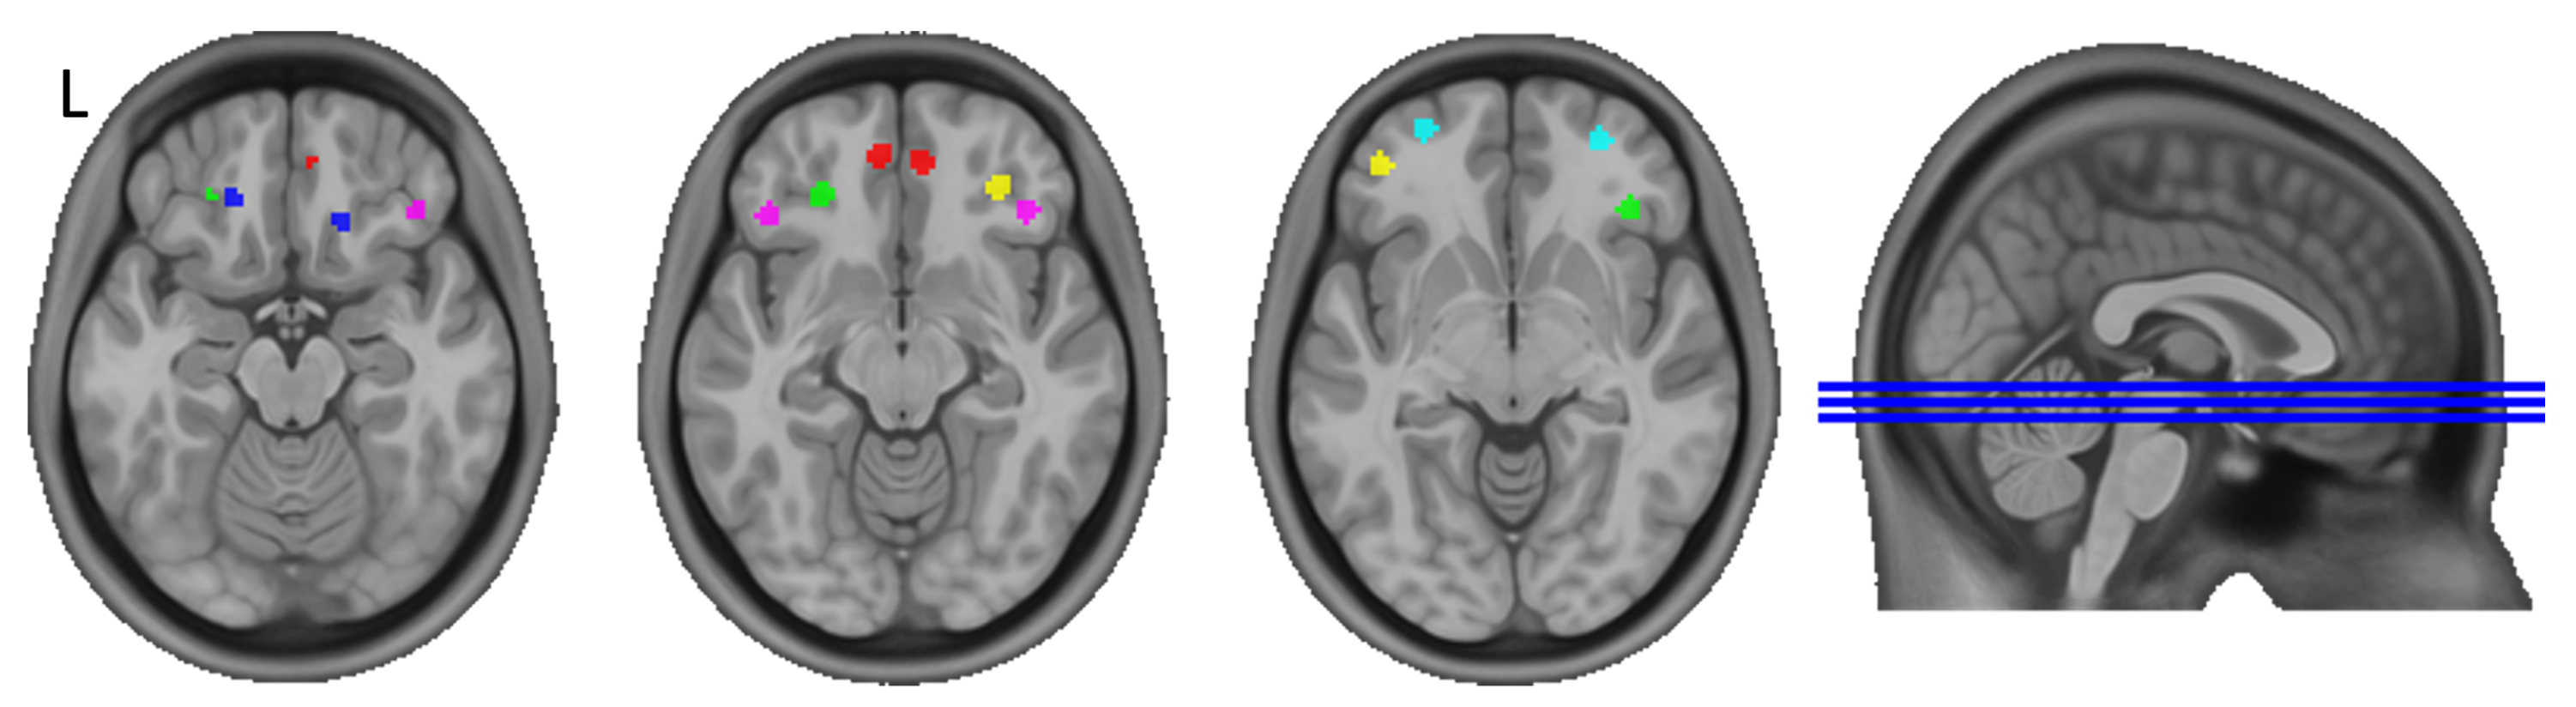

3.3. Seed-to-Whole-Brain Analysis

3.4. Post-Hoc Analyses